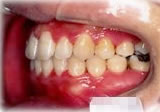

反対咬合(受け口)症例

初診時年齢24歳6ヶ月。前歯部反対咬合を主訴に来院。

骨格性反対咬合と診断し、外科的処置を併用して治療。

左側面 左側面 左側面